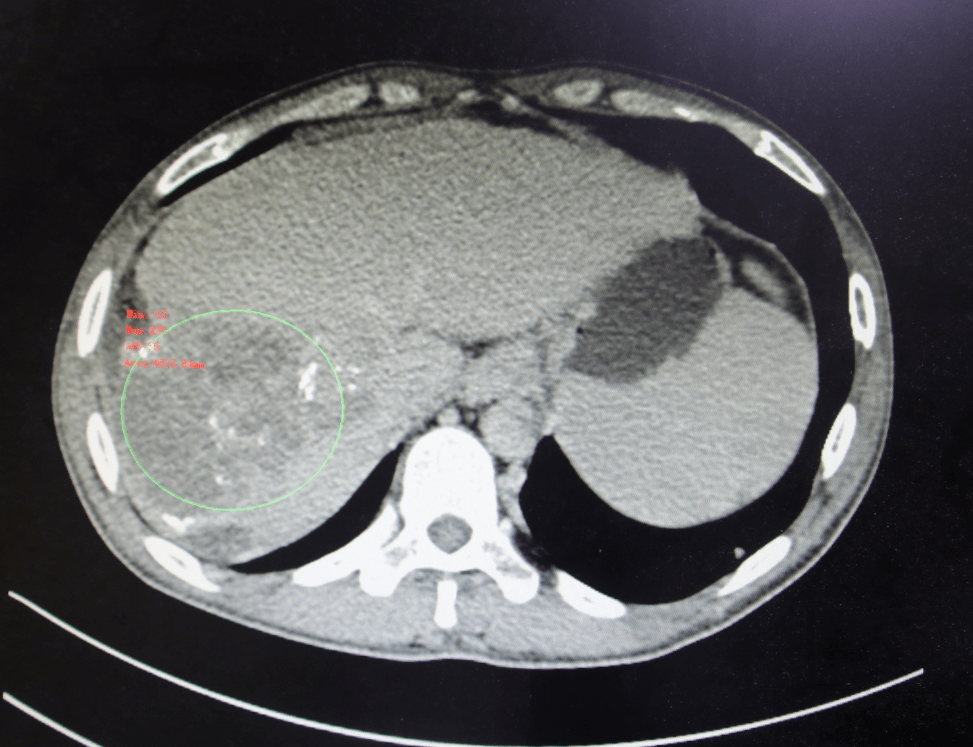

图22 肝转移瘤

肝脏多发转移瘤(图)

肝转移瘤

肝切除术后肿瘤肝内转移的影像表现